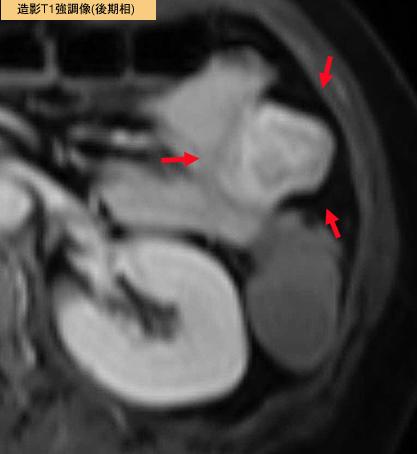

症例提示(所在地,施設名等): 福岡県・ 九州医療センター (Dr.平賀)

疾患(病理主体)の分類悪性非上皮性腫瘍/平滑筋肉腫(含GIST)

部位(臓器別)小腸/空腸

検査方法MRI

病変の最大径(ミリ)30〜34

腫瘍の深達度s(a)